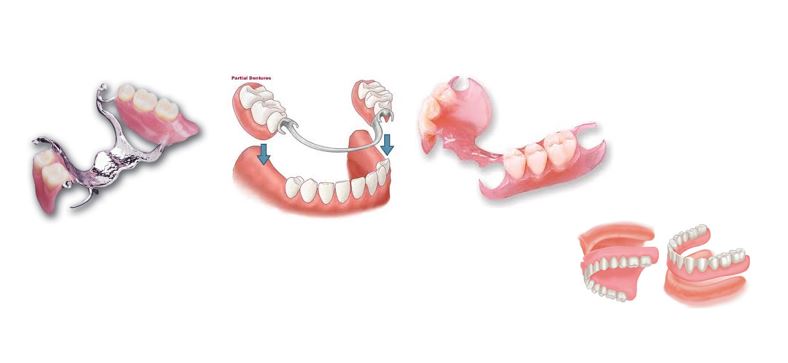

- Суулгадаг шүдэлбэр